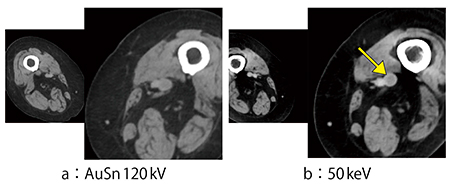

症例3は,肺動脈血栓塞栓症疑い症例である。高齢で腎機能が低下していたため,造影剤は240mgI/mLを100mL投与し肺と下肢の造影CTを施行した。AuSn120kV画像では,肺と下肢のいずれも血栓は不明瞭であるが,50keV画像では,特にコロナル画像において明瞭に肺動脈の血栓を指摘可能であり(図4),下肢についても血栓がはっきりと黒く抜けているのが確認できる(図5)。

図5 症例3の下肢画像